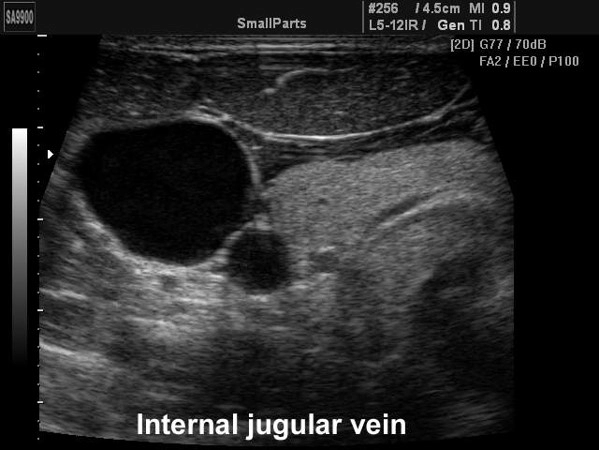

Обеспечение сосудистого доступа – аномальное расположение сосудов

Возможные пути решения проблемы:

- Использование УЗИ навигации при установке центрального венозного катетера и артериальной канюли.